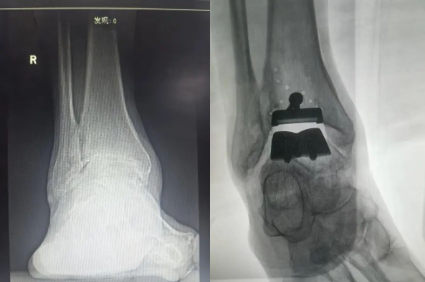

近日,济宁市第一人民医院手外科足踝外科主任曾文超教授团队成功应用3D打印技术,为一名77岁的严重右侧踝关节骨性关节炎患者成功实施了3D打印全踝关节置换手术,比传统踝关节置换时间减少90分钟,比术前踝关节活动度增加30度,标志着手外足踝外团队在关节重建领域迈入“个体化精准修复”新阶段。

今年77岁的患者鲍先生,右踝关节疼痛8年余,踝关节疼痛逐渐加重,目前仅能行走100米就会出现疼痛不能行走,因踝关节活动受限,不能上坡,严重影响了患者的日常活动。为求进一步治疗,患者来济宁市第一人民医院手外科足踝外科就诊。详细沟通后,患者对关节活动度要求高,希望尽可能恢复正常行走功能。经手外科足踝外科曾文超教授团队深入讨论后,决定采用3D 打印技术辅助全踝关节置换术。

术中应用术前设计好3D模具设计截骨走形,置入截骨导板,精准截骨纠正患者距骨外翻力线,手术过程顺利。术后假体位置及力线良好,肢体畸形明显纠正。

随着人工智能兴起,数字骨科逐渐成熟,术前根据踝关节CT数据,3D建模,模拟截骨推演术中截骨矫正力线,从而缩短手术截骨调整力线时间,提高截骨精准度。此次手术的完成,填补了鲁西南地区在该领域的医疗技术空白,济宁市第一人民医院手外科足踝外科继成功开展全踝关节置换技术后,在足踝疾病诊疗领域再次取得的重大突破。